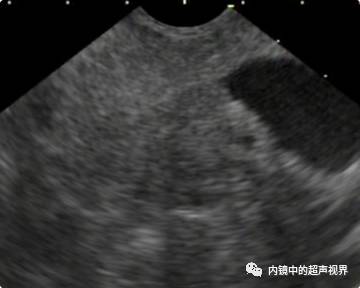

我现在使用的超声内镜DR可调节范围为30-90。以下三张图片显示的是同一个胰头肿物,肿物回声与胰腺回声非常接近,DR分别为90、70、40,其它参数相同,您更喜欢哪一张。

胰头占位